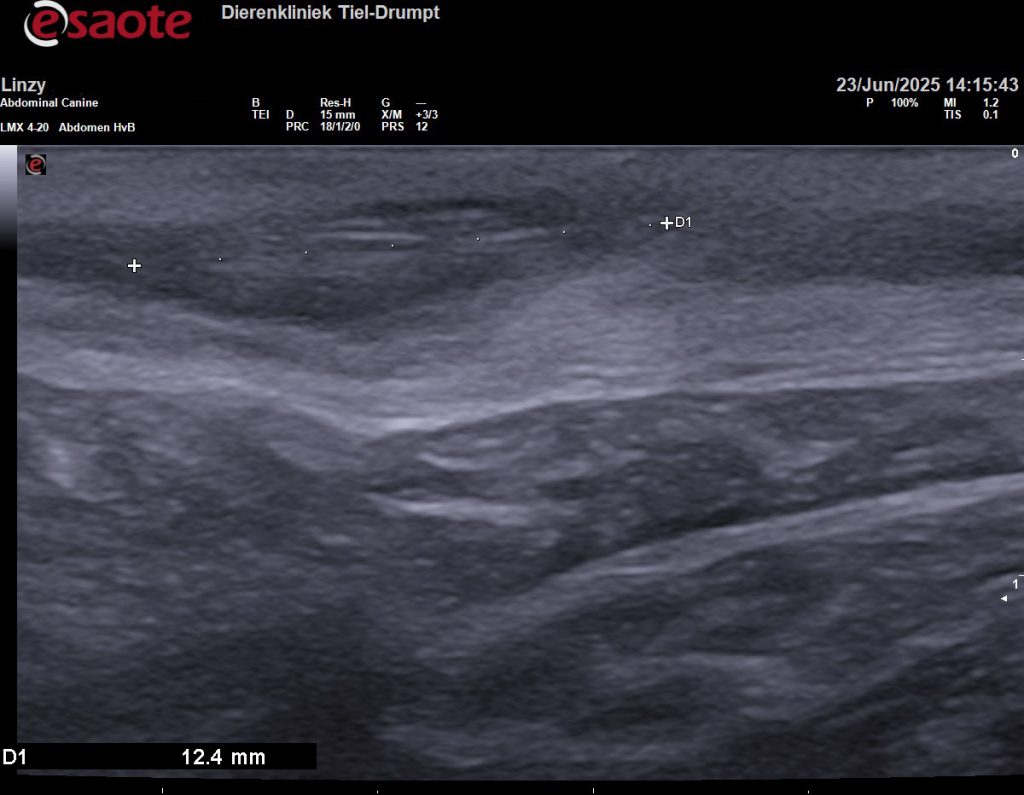

Om meer duidelijkheid te hebben, om te voorkomen dat we voor niks chirurgisch zouden ingrijpen, hebben we de plek eerst bekeken met een echo. Gelukkig hebben we ook een echokop voor zeer veel detail en het beeld bleek eigenlijk heel goed bij een grasaar te passen.

Om zeker te weten dat we alles hadden is het weefsel geopend, voordat we de wond gingen sluiten. In eerste instantie leek het alsof er geen grasaar in het weefsel zat. Maar dit liet maar weer zien hoeveel ons echoapparaat kan vergroten, want op de echobeelden is de diameter van de grasaar 1,5 millimeter en 12,4 millimeter lang. Na een paar sneden vonden we het steekkanaal en de daadwerkelijke grasaar.